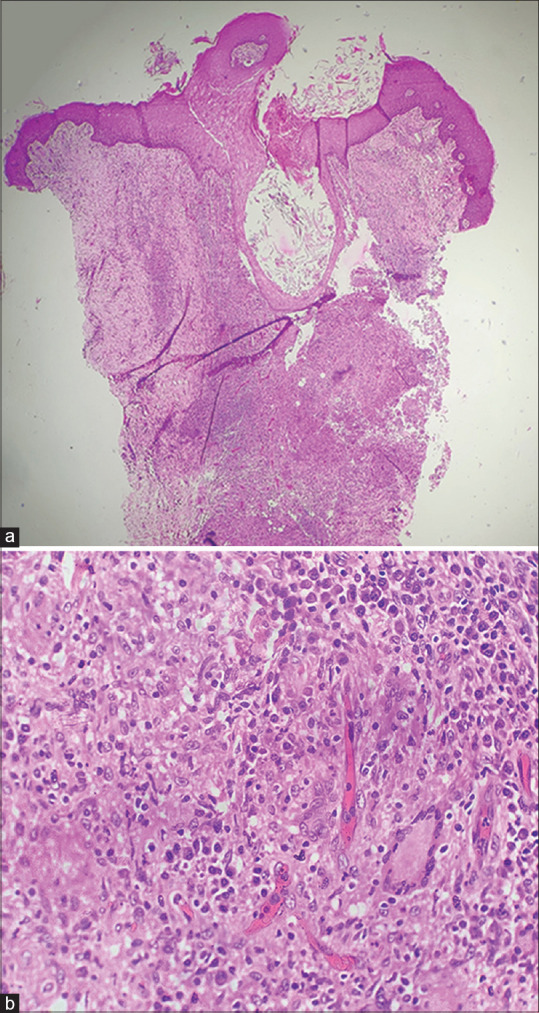

Trans-Epidermal Elimination Due to Insulin Formulation: Report of a Rare Adverse Effect.